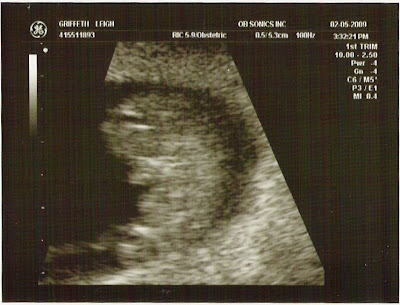

Reality is finally setting in for me, and the excitement. I guess it's about time, considering I'm already over 3 months now. Time flies and this has been pretty crazy. The baby is so big, and again they tell me, VERY ACTIVE. We've had two ultrasounds, and both of them showed the baby wiggling, waving, and moving all around. Babies are truly a gift from God and I could sit there for hours just watching in amazement, thinking I still can't believe that little thing is inside me. We have lots to look forward to, and lots to get ready for. It looks like Spence is going to have a new room sooner than we thought, but I'm sure he will adjust fine. He's going to be the best big brother.

The appointments all went very well, except for Spence getting very upset during our first U/S when he saw the lights go off, I layed down on the table, and all of a sudden this lady is doing weird things to mama. He was very confused and VERY upset until I sat up and the lights came back on. Needless to say, my second U/S was great and Dr. Barrett spent a lot of time with me explaining things. Both, the baby and myself, are doing great right now.